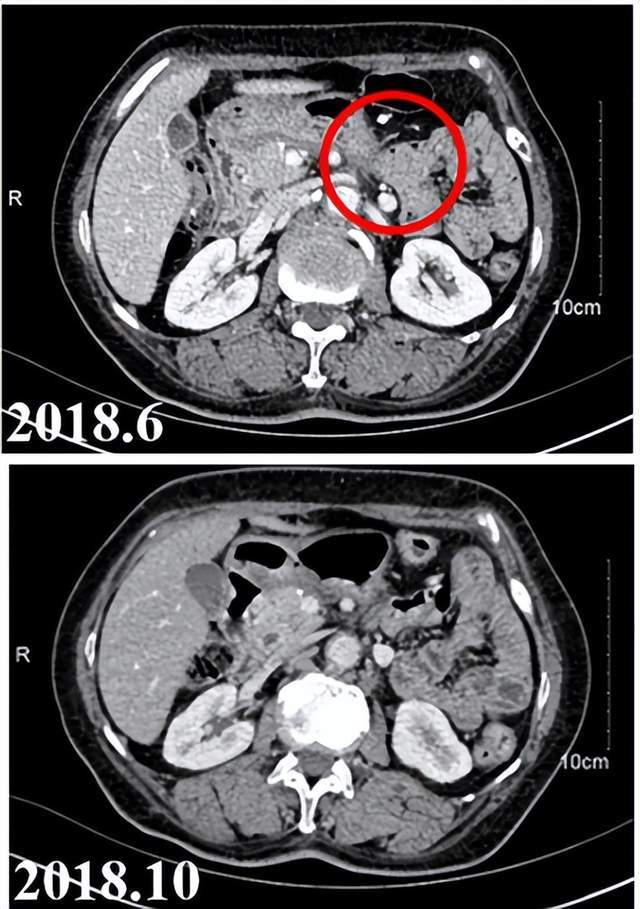

其中一名患者于2017年7月首次诊断为胰腺癌伴肝转移。既往接受化疗与胰腺切除术。然而仍旧进展,发现淋巴结转移。于是该患者接受了iNeo-Vac-P01治疗,并达到部分缓解(PR)状态,靶病灶大小较治疗前减小了54%。